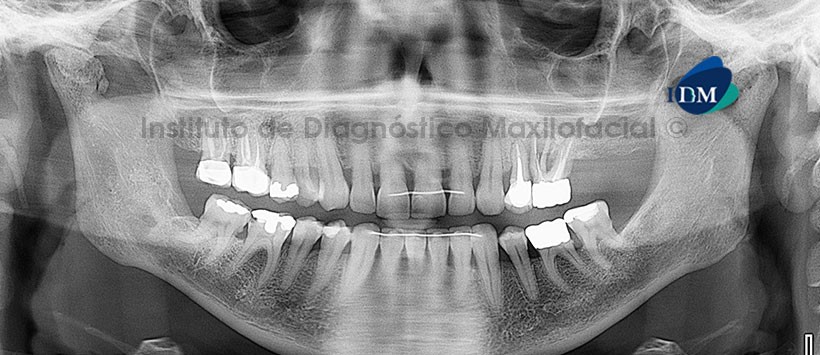

A la evaluación de la radiografía panorámica (Figura1) observamos múltiples zonas radiopacas de densidad ósea proyectadas por delante de la ATM derecha, donde se puede apreciar también , un aparente proceso degenerativo articular.